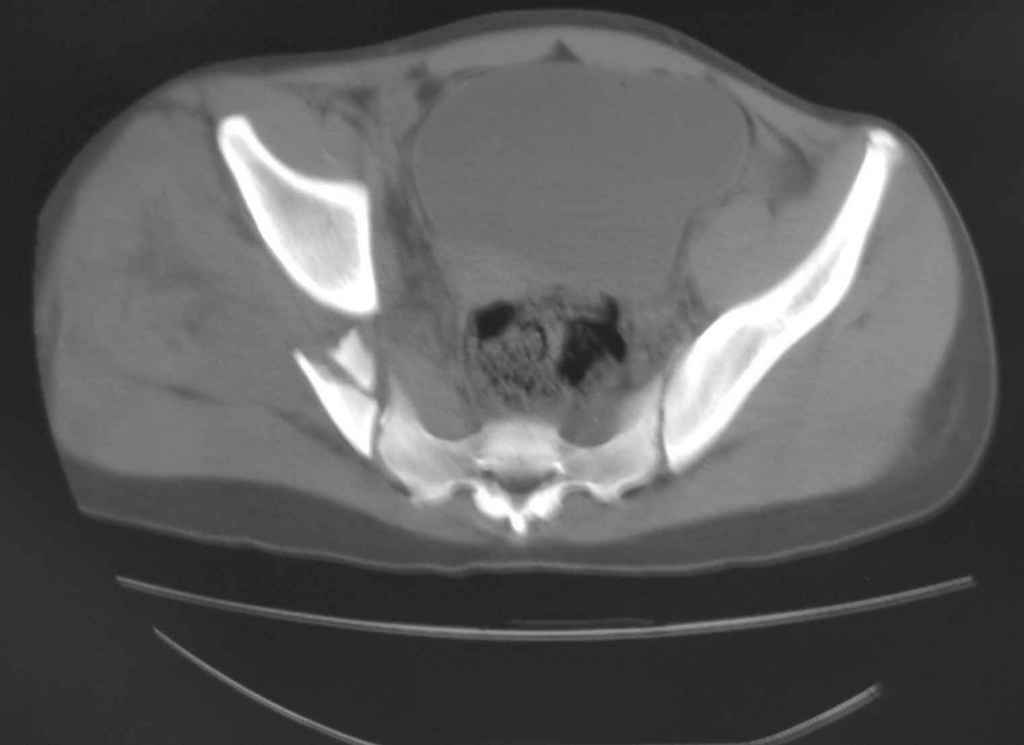

Ребенок 13 лет Перелом костей таза.

Уважаемые коллеги, в нашу клинику поступил ребенок 13 лет; травма четыре дня назад(падение с 5-го этажа). Помогите определиться с дальнейшей тактикой.